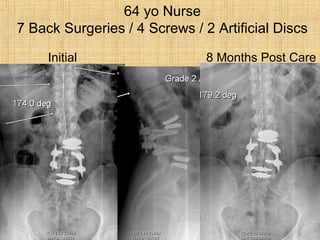

64 yo Nurse

7 Back Surgeries / 4 Screws / 2 Artificial Discs

Initial 8 MonthsPost Care 64 yo Nurse 7 Back Surgeries / 4 Screws / 2 Artificial Discs